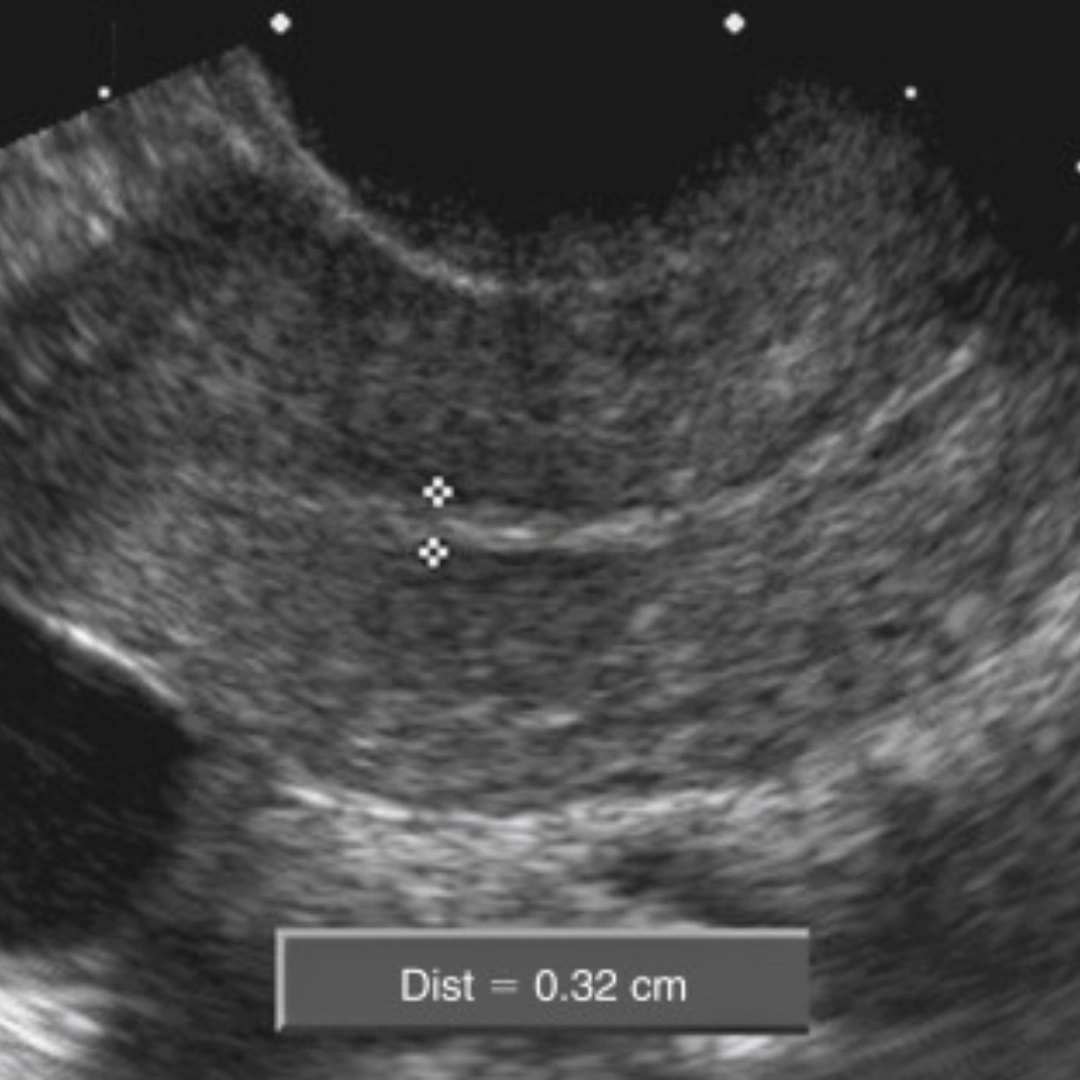

– Suspected molar pregnancy or abnormal ultrasound findings.